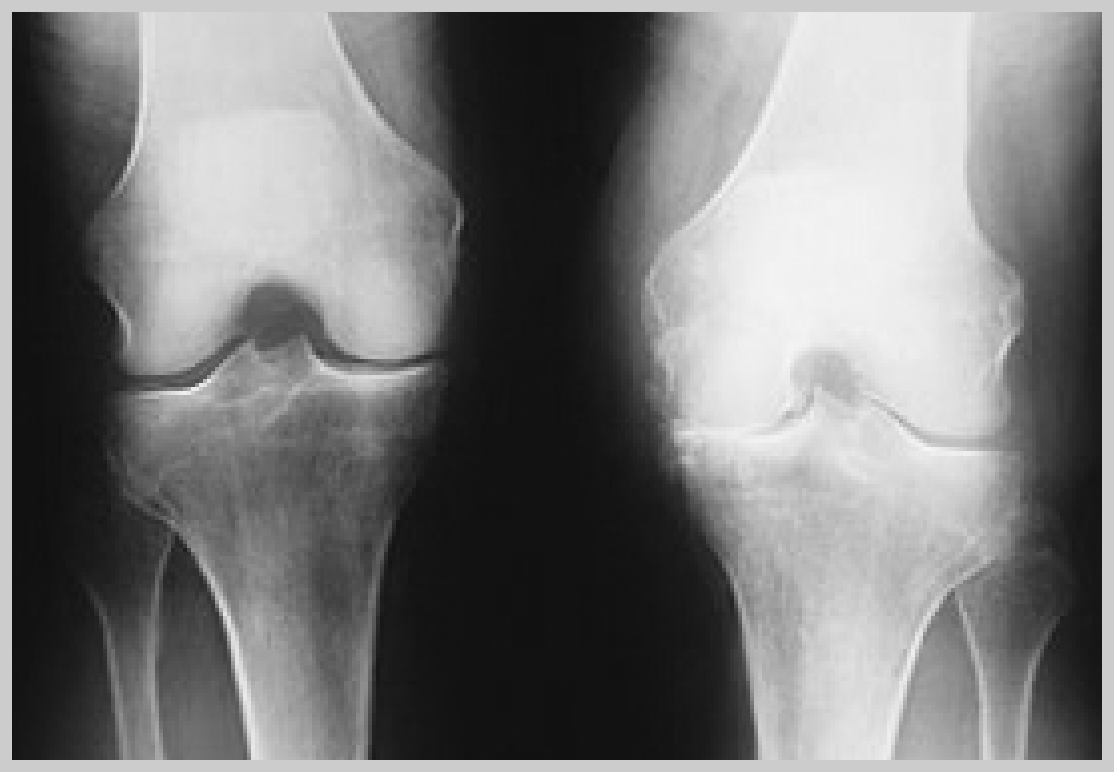

Das Kniegelenk ist das größte Gelenk des menschlichen Körpers. Seine Entwicklung ist über 4 Millionen Jahre alt. Gleichzeitig muß es Stabilität, aber auch Beweglichkeit gewährleisten. Sowohl Verletzungen, aber auch Verschleiß, führen zu Schmerzen und Bewegungseinschränkung.

In vielen Fällen  wird dabei der Meniskus und /oder der Knorpel, aber auch die komplizierten Bandstrukturen des Kniegelenks in Mitleidenschaft gezogen.